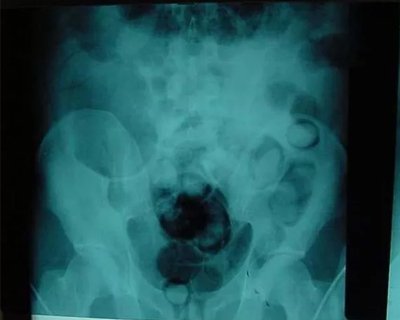

В Казахстане узбекистанец пытался провезти марихуану внутри себя, но не смог